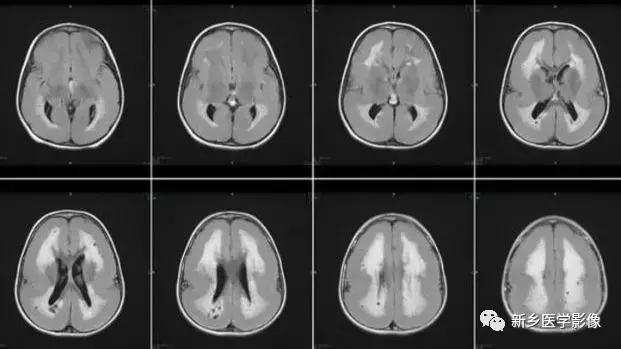

6.脑室周围白质软化症

主要与缺血缺氧及感染有关。

常见于早产儿。常见于早产儿的原因与胚胎期脑部损害发生的时间有关,胚胎早中期脑损害主要引发发育畸形,晚期主要引起脑血管改变。

由于脑室周围白质的血供分别来自脑室区和远脑室区的终动脉,未成熟儿终动脉深穿支的侧支循环尚未建立,而胚胎晚期脑室周围白质对缺血缺氧敏感。所以,脑室周围白质软化症多见于早产儿。

由于侧脑室周围有软化萎缩,故扩大的侧脑室外缘常不规则,不光整,这种不规则、不光整是本病引起脑室扩大的特征,另外,本病均表现有脑白质量减少及脑白质内斑片状软化病灶,脑白质减少严重时表现为部分区域白质消失,脑皮层与脑室侧缘接近甚至相连。CT表现为斑片状低密度灶。MR T1WI上呈低信号,T2WI呈高信号。